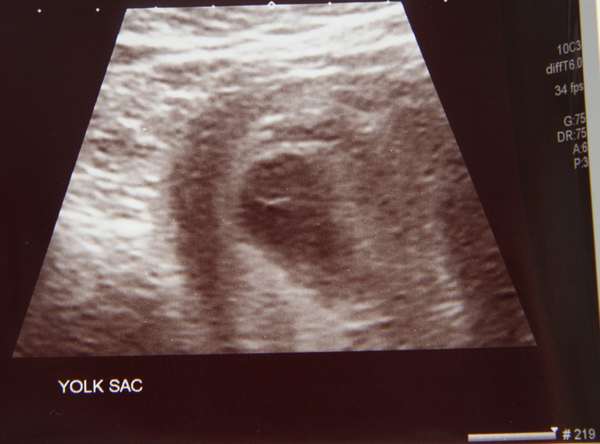

Trying to hold it together here. The scan was inconclusive as they said it may be too early to see anything yet. They saw a yolk sac measuring 6w6d but they couldn't see anything inside it. There was a midwife there training to use the sonography equipment and she was doing the scan, she said directly to me 'its not an empty sac' in a way that was supposed to give me encouragement. They asked me if i felt reassured and I said no because I've seen 2 yolk sacs before and they ended in miscarriage. I really wanted them to say they could see an embryo or a heartbeat. At one point the student said to the monographer 'is that?' and he said 'yes'. I think he said 'it looks like it could be a developing embryo' but I'm not even sure if he did say that now. They also said in a reassuring way 'this is normal for a healthy pregnancy'. The yolk sac measures 16.5mm / 6w6d.

They gave me a scan photo which I'll upload so you can see. It's just a yolk sac. It's pretty poor quality.

I just wanted to say it was the gestational sac that measured 6w6d not the yolk sac. Early to bed tonight - a new day tomorrow. x

Annie. Sorry for the news. But with a sac which is less than 21mm in diameter no sonographer should say anything negative about what might happen. A yolk sac means no blighted ovum. Also, there is the dual halo around tour sac, it is a live embryo right now. At the sid eof yolk sac there is a thicker place, which might be why they thought it is a developing fetal pole and it may well be. A fetsl pole less than 7mm does not need to have a heartbeat at all. So, it can turn out alright. It can of course go badly and I wouldbe worried shit (and indeed I was when I have seen such US too late acc. to my own calculations), but now it depneds basically whether it is a natural late developer or something is wrong with it, in which case it stops developing. None can tell anything from this scan. I guess why the nurse said that the doc said you must expect to bleed, is your hcg. They think that with hcg above 20 000 heartbeat should be present. It normally is when you exceed 10 000. But betas are very variable, which means that one might get a hb with beta of 6000 and the other need to wait until 100 000.

Do you agree w 6w6 days of gestation? Or you think you are less or more gone. It puzzles me they put your 16mm sac at 6w, I think I have been given 5w6d with 16 mm, which only shows that different docs use diff. standards here as well.